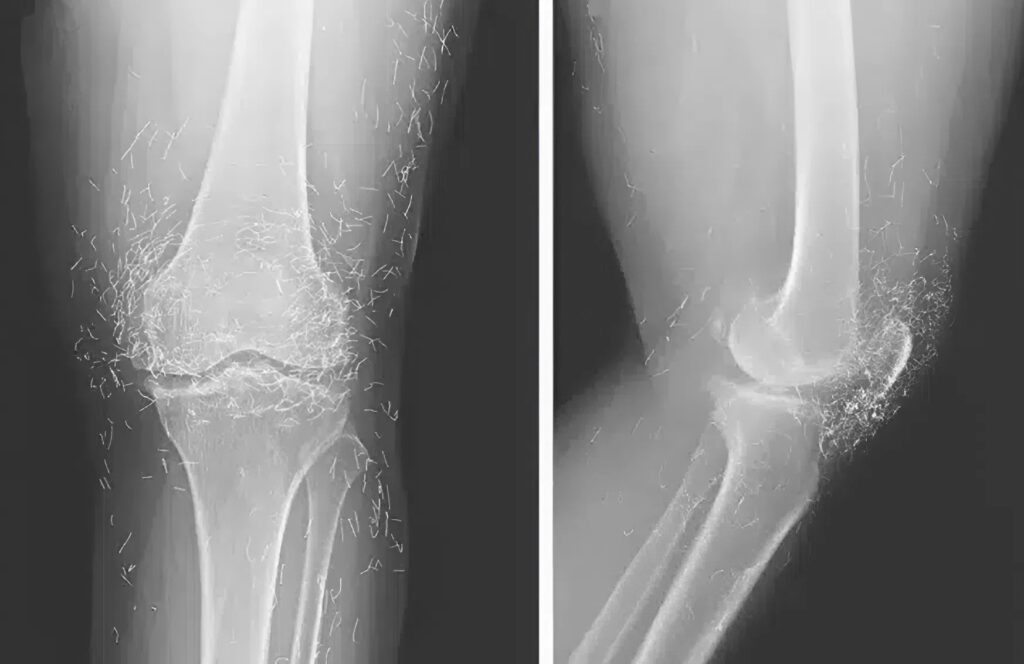

Quando recebemos a imagem, um silêncio pairou no consultório. Na tela, podia-se ver claramente algo que simplesmente não poderia estar ali — como se sombras metálicas se entrelaçassem nos tecidos da perna.

No começo, pensamos que o aparelho estava com defeito. Repetimos a radiografia — o resultado era o mesmo.

Quando finalmente entendemos o que estávamos vendo na radiografia, um calafrio percorreu nossas costas.

Nos tecidos do joelho brilhavam dezenas de pequenos objetos — em fileiras perfeitas, como se alguém os tivesse inserido sob a pele de propósito. Ampliamos a imagem — eram agulhas de ouro.

A paciente, confusa, admitiu: alguns anos atrás, havia feito tratamento com um “acupunturista famoso”, que garantiu que, se deixasse as agulhas no corpo para sempre, elas “estimulariam continuamente os pontos” e eliminariam a dor para sempre.

Agora seu joelho estava inflamado, os tecidos ao redor começaram a se deformar, e qualquer tentativa de dobrar a perna causava dor intensa. Explicamos que o corpo percebeu o metal como uma ameaça e começou a combatê-lo, encapsulando cada agulha em tecido denso.